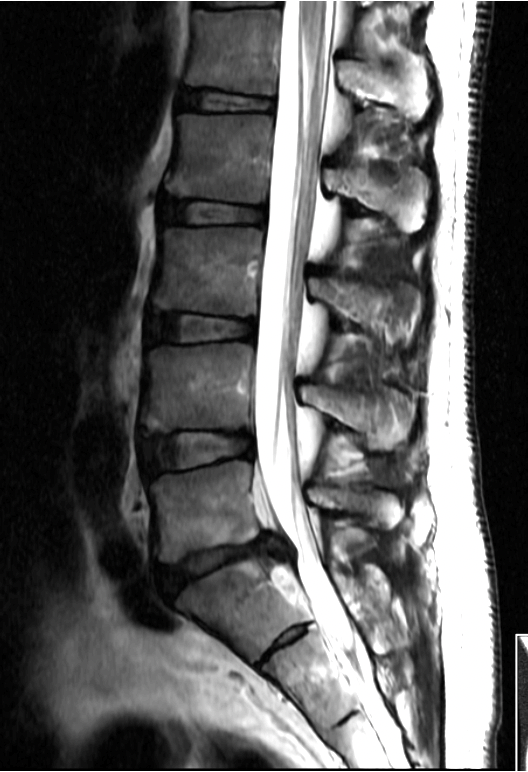

MRI scan showing side view of human lower spine and lumbar region.

• MRI of the lumbar spine

MRI helps identify disc herniation and nerve compression.

• MRI is the best test to confirm the diagnosis